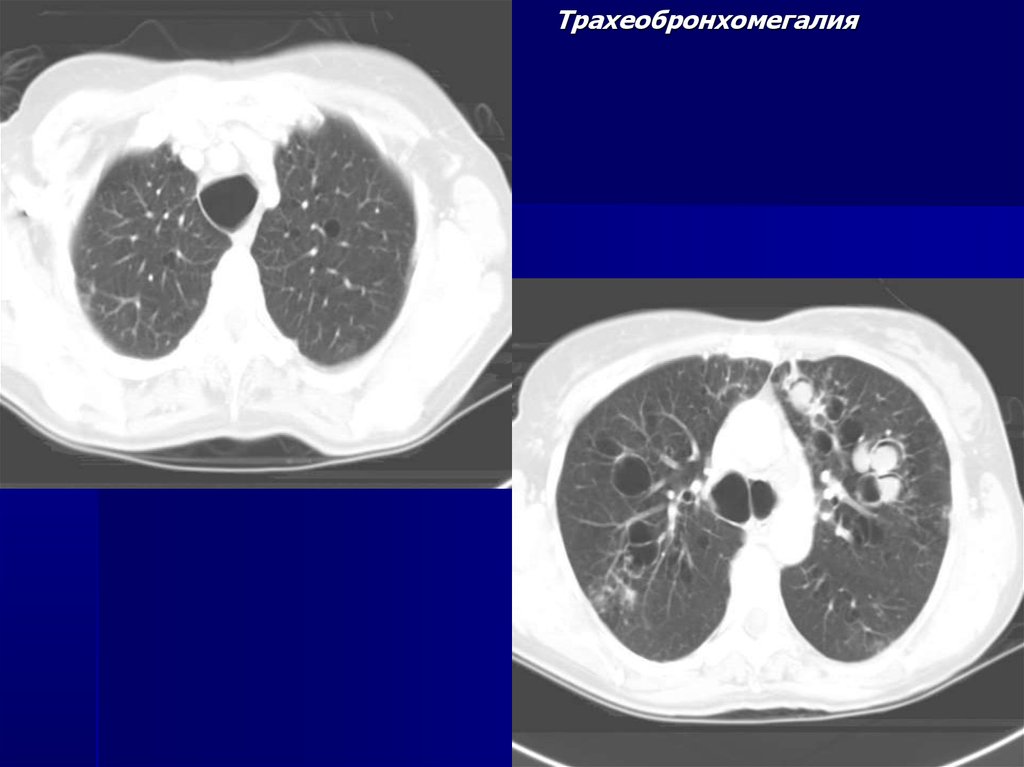

Трахеобронхомегалия